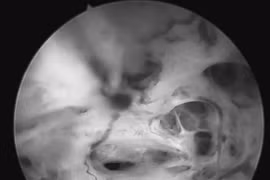

Nội soi siêu âm giúp phát hiện sớm ung thư tụy, dạ dày, đại trực tràng, nâng cao hiệu quả điều trị và giảm chi phí y tế dài hạn